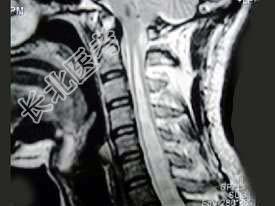

- 单项选择题男,27岁, 常有手、臂的自发性疼痛、麻木、蚁走等感觉异常,结合MRI检查, 最可能的诊断是 ( )

B、脊髓空洞症